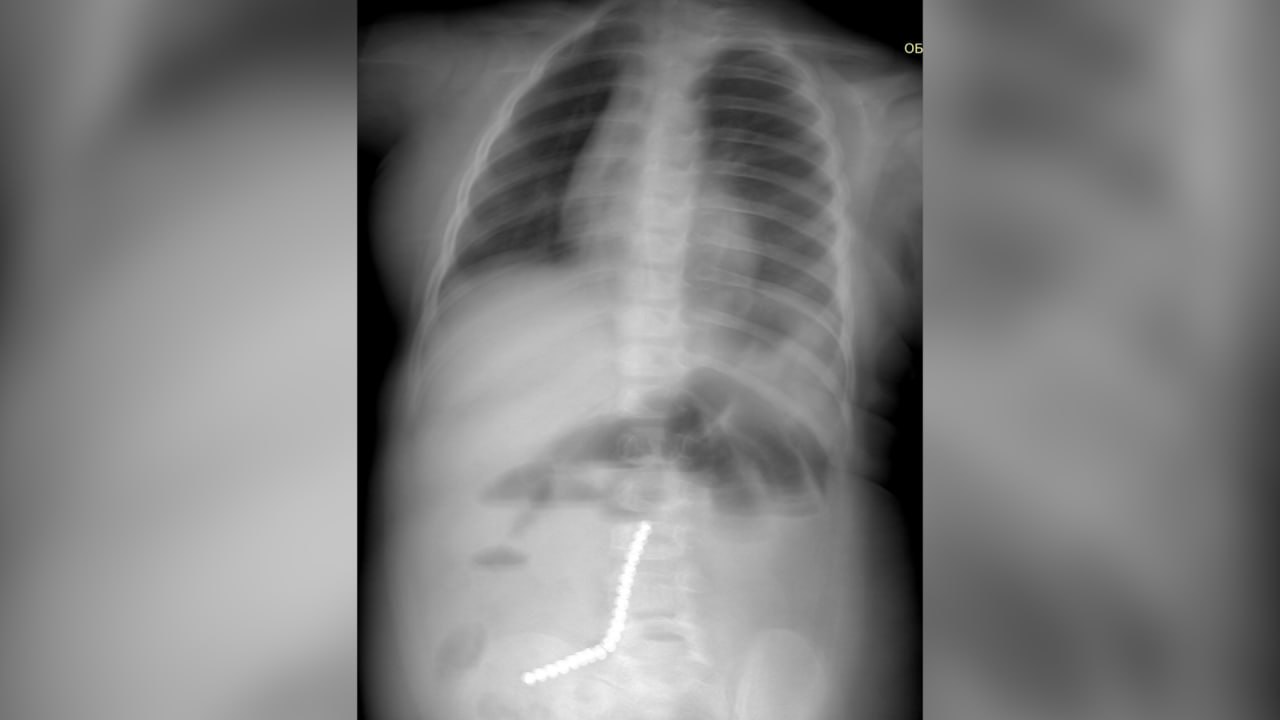

В Бурятии врачи спасли двухлетнего ребенка, проглотившего 20 магнитных шариков от неокуба. Подробности сложнейшей операции сообщили в Детской республиканской клинической больнице.